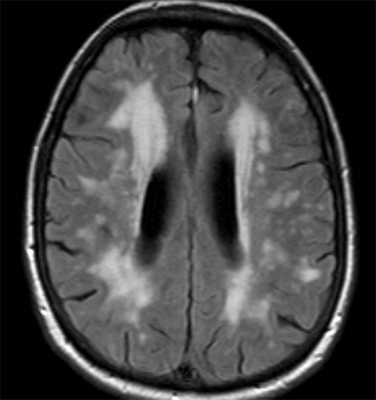

- Индекс паркинсонизма - отношение ширины верхней ножки мозжечка в корональной плоскости к площади среднего мозга в средней сагиттальной плоскости умноженной на отношение ширины средней ножки мозжечка к ширине верхней ножки мозжечка - больше 13,55 свидетельствует в пользу паркинсонических синдромов. При МРТ выявляется атрофия хвостатых ядер с вторичным расширением передних рогов; атрофия скорлупы и коры лобных долей. Отношение ширины передних рогов к расстоянию между хвостатыми ядрами (по их краям), измеряемое в поперечной плоскости уменьшается с 2,2-2,6 до значений близких к 1,0. Другой коэффициент - расстояние между хвостатыми ядрами (между их головками к ширине черепа по внутренним пластинкам) - увеличивается (в норме 0,09-0,12).При МРТ головного мозга выявляется диффузная атрофия мозга, расширение периваскулярных пространств Вирхова- Робена и лейкоараиоз. Последний является следствием стеноза и окклюзии глубоких вен мозга. На Т2-зависимых МРТ изображениях лейкоараиоз выглядит как небольшие очаги гиперинтенсивности. В целом эти признаки неспецифические и отражают старение мозга. При МРТ головного мозга на томограммах обоих типов взвешенности обнаруживается повышенный сигнал от моста и покрышки мозжечка. Типично изменение сигнала от периферии моста. В отличии от опухолей при МРТ нет отека и масс-эффекта. Самые ранние проявления обнаруживаются на диффузионное-взвешенных МРТ головного мозга, примерно через 24 часа от начала тетрапареза.

Болезнь Бинсвангера (субкортикальная атеросклеротическая энцефалопатия, деменция мелких сосудов). Это состояние, связанное с множественными инфарктами мелких ветвей, что при МРТ головного мозга видно как лакунарные ОНМК. Заболевание постепенно прогрессирует. Вариантом болезни Бинсвангера можно считать наследуюмую семейную артериопатическую лейкоэнцефалопатию.

![Бинсвангер]()

МРТ головного мозга. Т2-взвешенная МРТ типа FLAIR. Болезнь Бинсвангера.